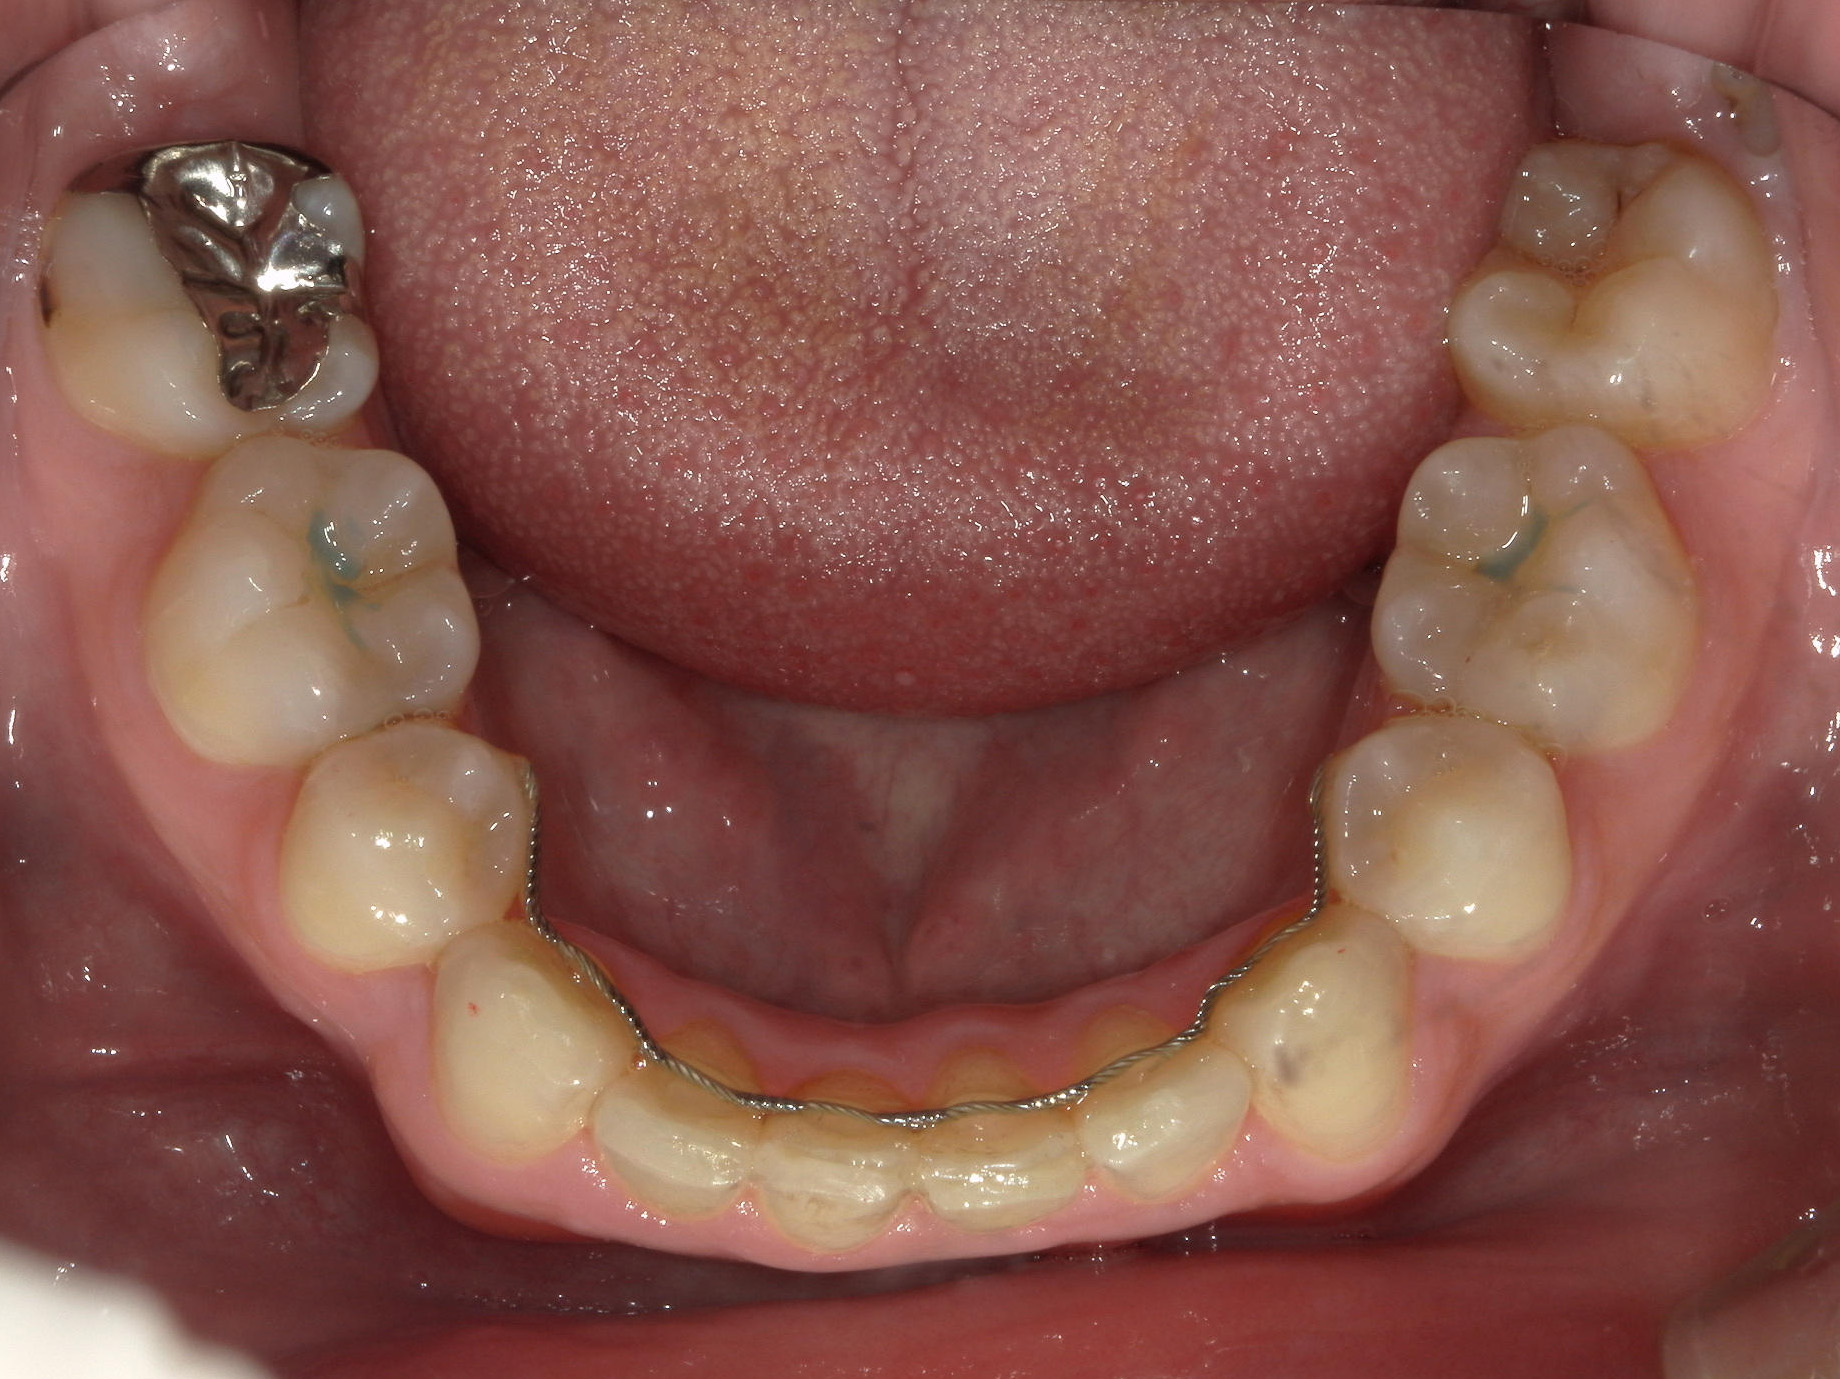

全顎ワイヤー矯正 症例(79)

主訴: 前歯が噛み合わない。歯並びが気になる。

上下左右 第一小臼歯(4本)、上下右 親不知(2本)抜歯。

ミニインプラント、アップライトスプリングを併用。

カテゴリー : ガタガタ(叢生) , 噛み合わせが深い(過蓋咬合)